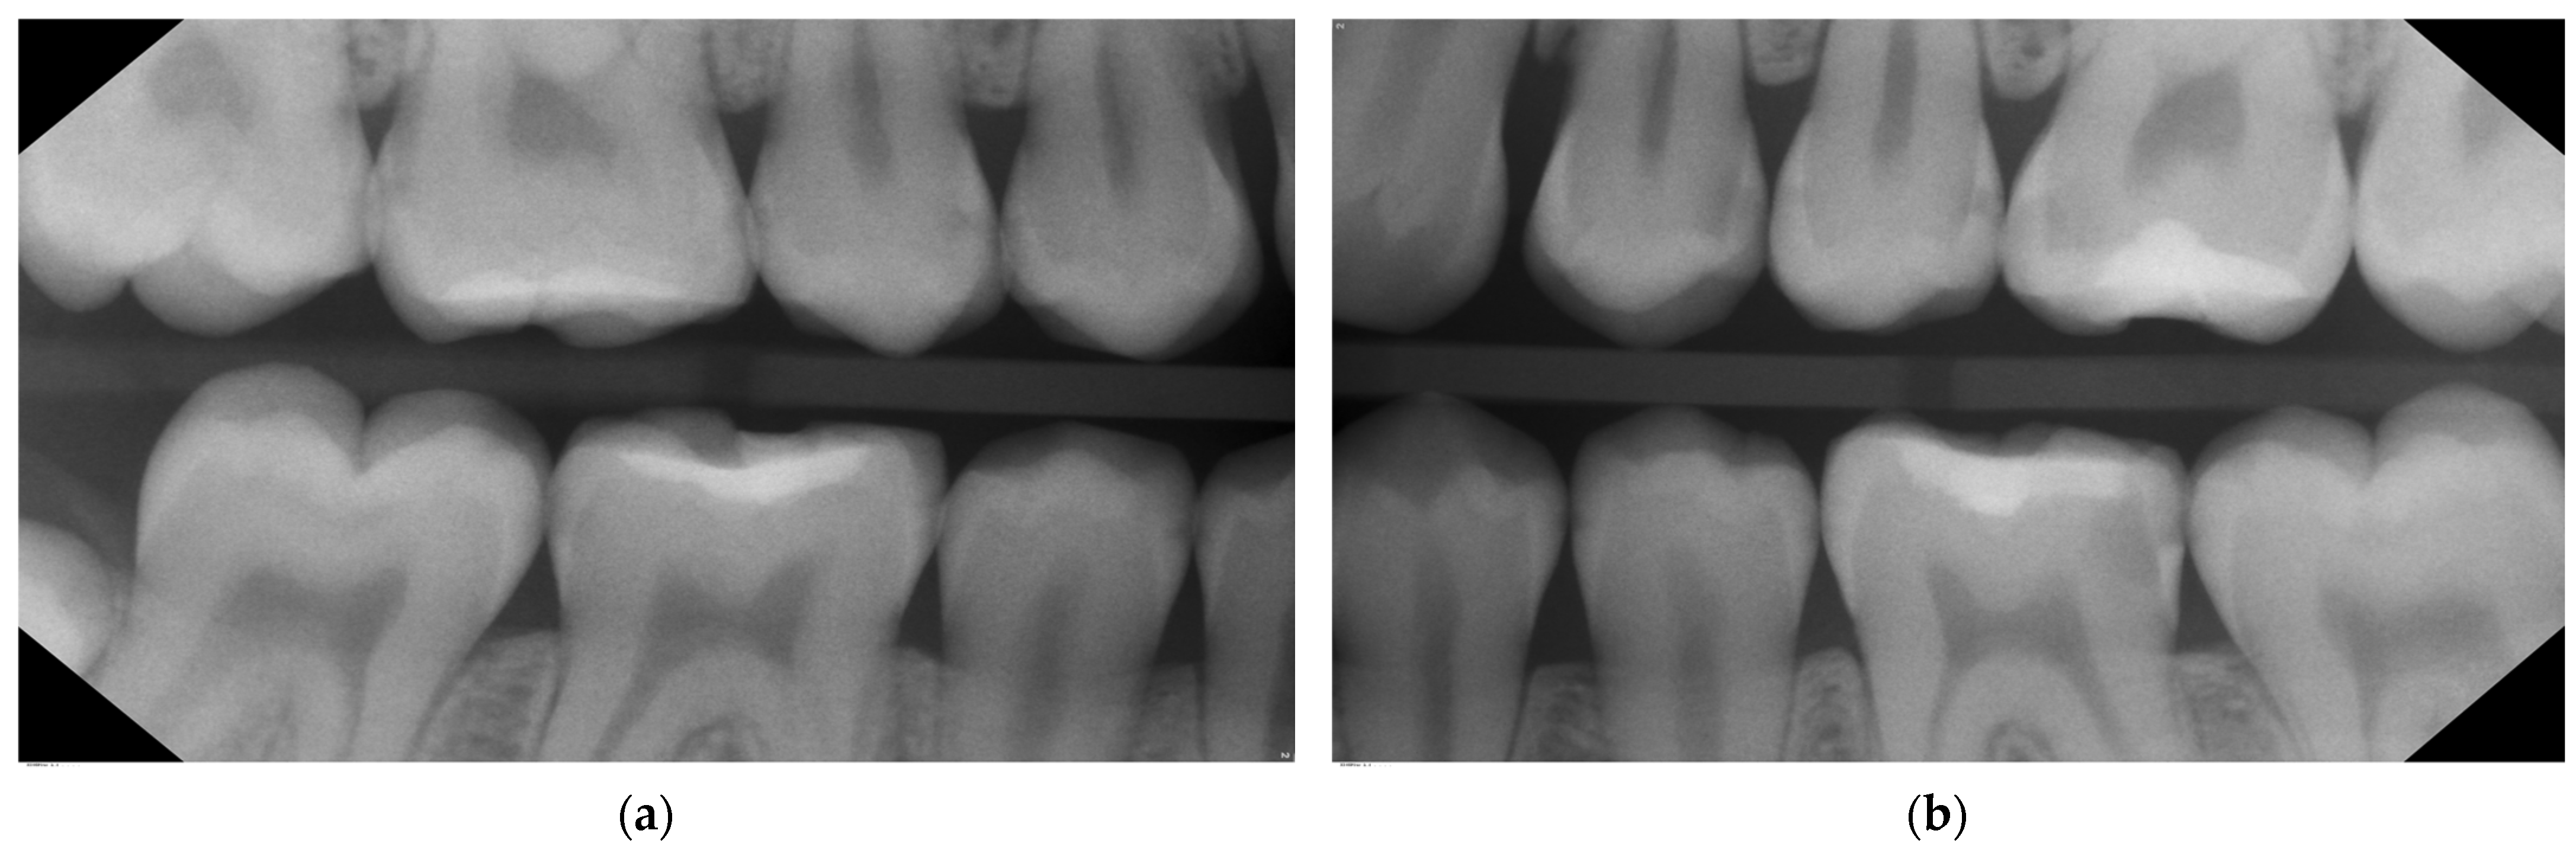

- Bitewings radiographs: During the same dental visit, bitewing X-rays were taken to confirm the presence of lesions and to determine their depth and proximity to the pulp (Figure 1). The ADA proximal caries classification system was used to diagnose and monitor progression of these lesions: E1: lesion in the outer half of the enamel; E2: lesion within the inner half of the enamel; D1: lesion passing the enamel dentin junction (EDJ) and within the outer third of dentin; D2: lesion within the 2nd third of the dentine; D3: deep lesion passing the 2nd third of the dentin [16]. For evaluations of the bitewing X-rays, three calibrated pediatric dentists classified the lesions independently in a dark room with the option to digitally modify the contrast and brightness of the X-rays. In the rare cases of disagreement, consent was reached via a discussion (Table 1). Bitewings were taken using a Sirona Heliodent DS and a Xios XG supreme intraoral sensor, with a standard dose of 0.16 mAs. The same criteria for bitewings were considered also for the follow-up visit which was at the same time the pre-SDF radiographic examination (Figure 2).

| Figure 7—02/2019 | 0 | 0 | E1 | 0 | 0 | 0 | 0 | 0 | 0 | 0 | E1 | D1 | 0 | 0 |

| Figure 8—03/2022 | E1 | D1 | E1 | E2 | D1 | E2 | 0 | 0 | D2 | D1 | D1 | D2 | E1 | E1 |

| Figure 10—03/2023 | E1 | D1 | E1 | E2 | D1 | E2 | 0 | 0 | D2 | D1 | D3 | D2 | E1 | 0 |

| Tooth | 47 | 46 | 45 | 44 | 34 | 35 | 36 | 37 | ||||||

| Surface | M | D | M | D | M | D | D | M | D | M | D | M | ||

| Figure 7—02/2019 | 0 | 0 | 0 | 0 | 0 | 0 | 0 | 0 | 0 | 0 | E1 | 0 | ||

| Figure 8—03/2022 | E1 | D1 | E1 | E1 | E2 | E1 | E1 | E2 | E1 | E1 | D2 | E1 | ||

| Figure 10—03/2023 | E1 | D1 | E1 | E1 | E2 | E1 | E1 | E2 | E1 | E1 | F | E1 | ||